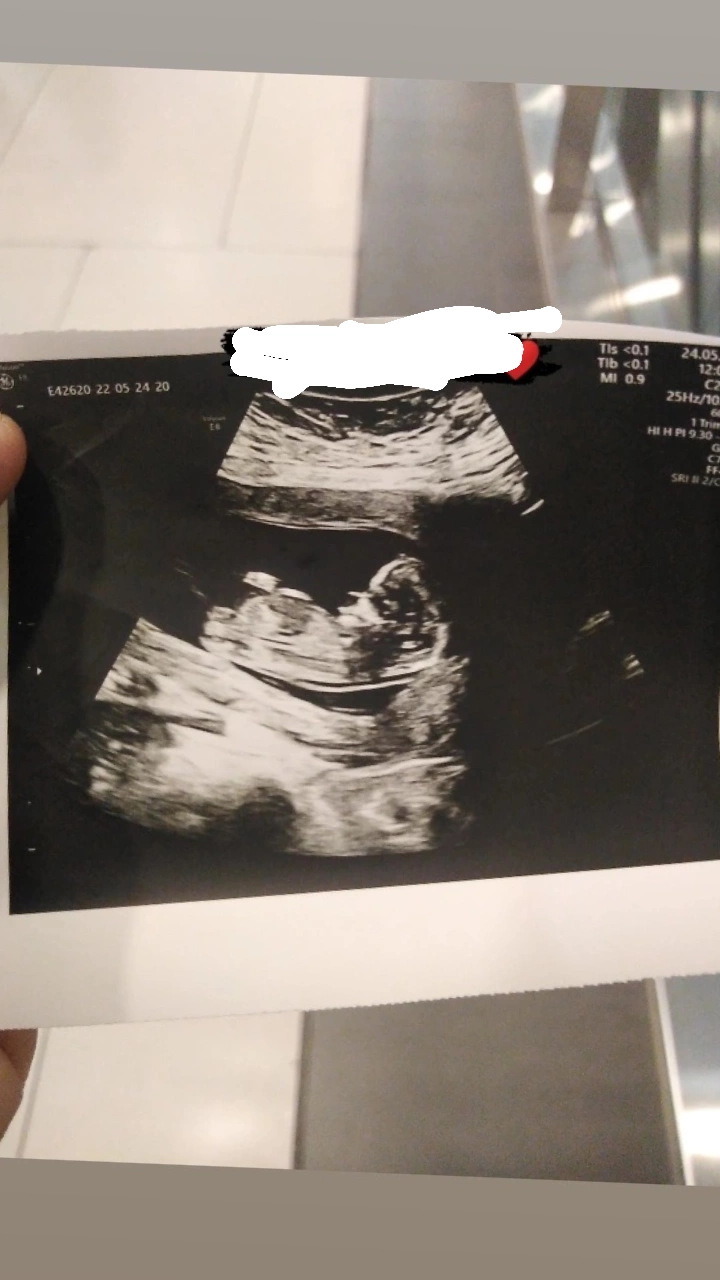

Ben birşey merak ediyorum dun doktora ilk defa gittim karından muayenede goremedı alttan muayenede 5 haftalık dedı ama ultrasyonda boyle kesenın ıcınde bırsey yok bombos duruyor adet tarıhıme gore hesaplama yaptı ama ben 5 haftalık oldugunu sanmıyorum